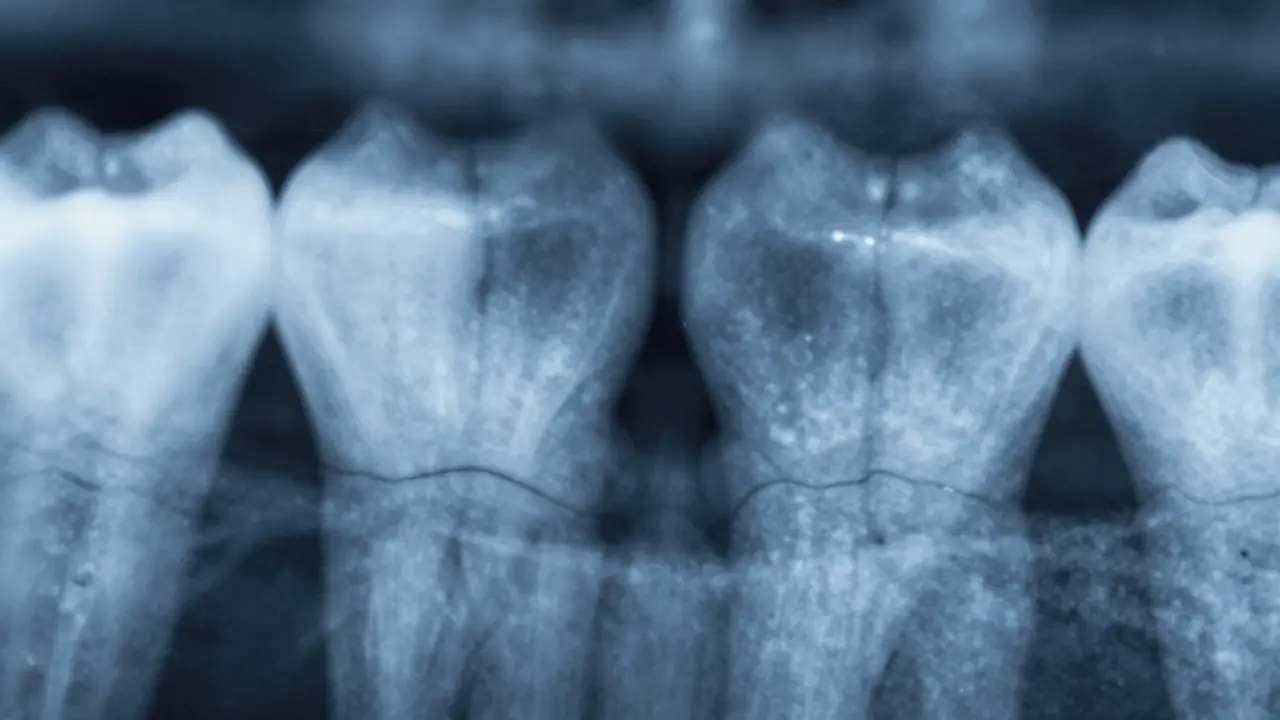

Jak vypadá mezizubní kaz na rentgenu?

Nejspolehlivější způsob, jak mezizubní kaz detekovat, je rentgen. Na panoramatickém nebo bitewingovém snímku vypadá jako tmavá, nepravidelná skvrna mezi dvěma zuby. Nejčastěji je vidět jako „černá škvrna“ nebo „výřez“ v místě kontaktu zubů. Čím hlouběji se kaz rozšířil, tím větší je tmavá oblast na snímku.

Na počátečním stupni je to jen tenká čára pod povrchem skloviny. V pozdějších fázích se stává širokou, tmavou oblastí, která sahá až k zubnímu nervu. Stomatolog na rentgenu hned ví, zda jde o malý, omezený kaz, nebo o rozsáhlé poškození, které vyžaduje kořenové léčení.

Je důležité vědět: na vizuální prohlídce, bez rentgenu, je mezizubní kaz často neviditelný. I když zub vypadá zdravě, může být uvnitř zničený. Proto je pravidelný rentgen každé dva roky nezbytný - nejen pro děti, ale i pro dospělé.